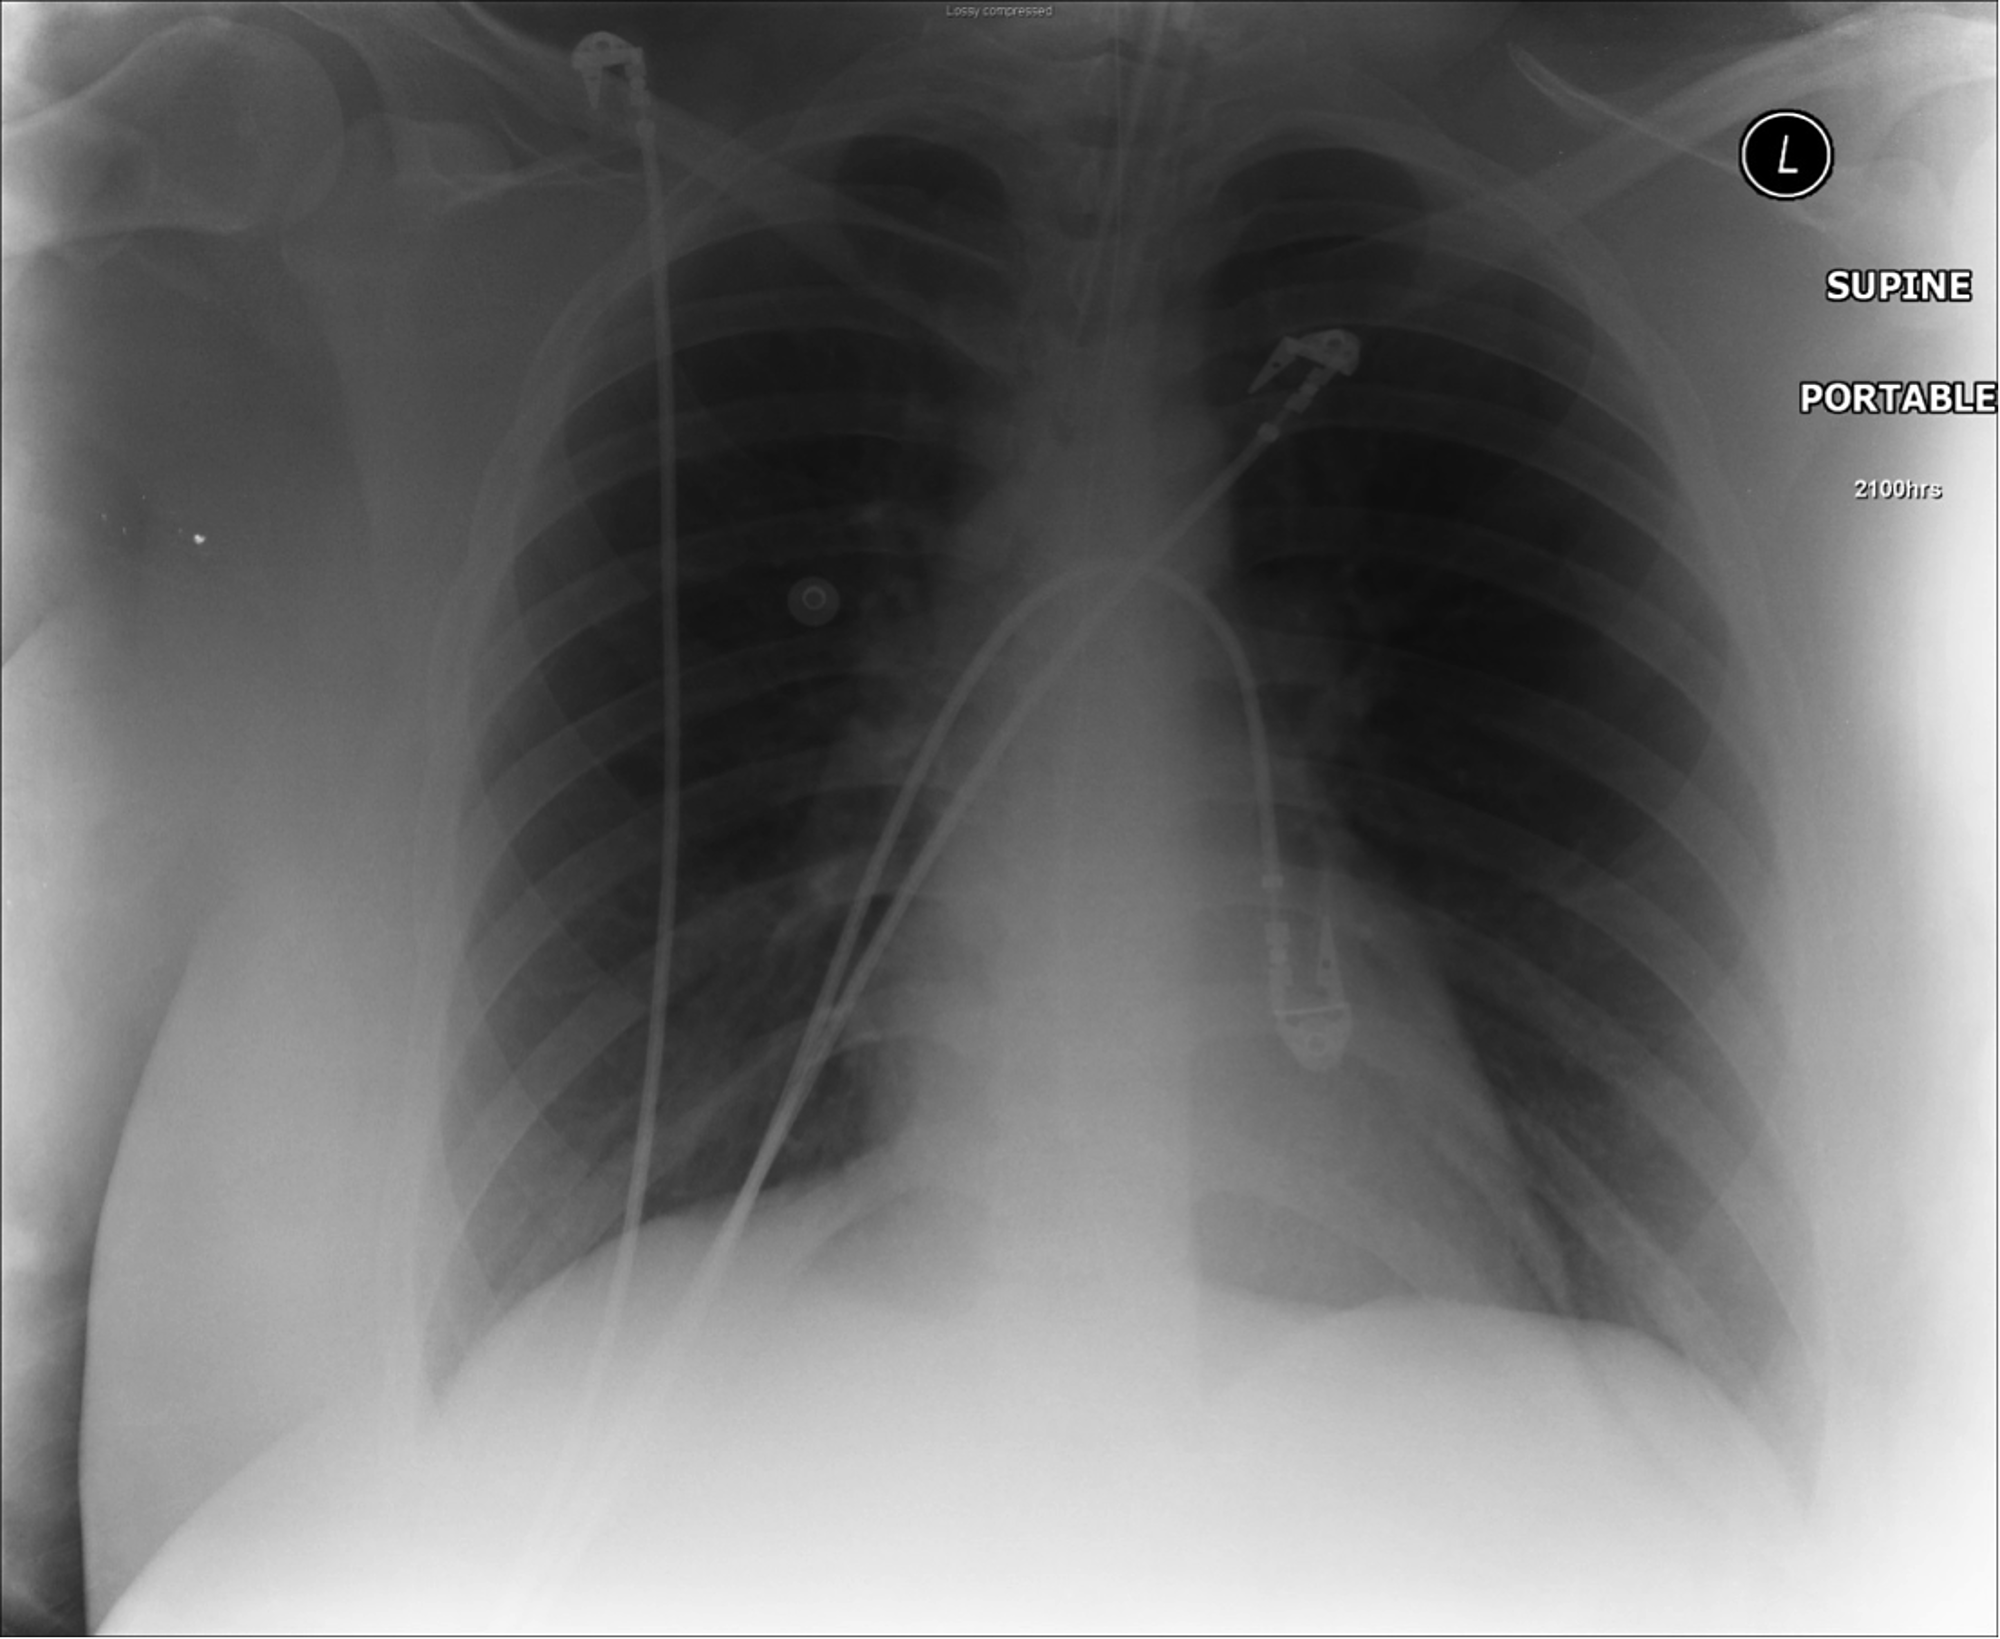

Asthma Chest X Ray Radiopaedia . Suspected pneumomediastinum, pneumothorax or surgical. — although bronchial thickening, hyperinflation, and focal atelectasis suggest asthma when they are present, chest radiographs obtained. Clinically, traditional chest radiography and computed tomography (ct) continue to play a key role in the. Chest radiographic findings in asthmatic patients are not entirely specific but, when present, include bronchial wall thickening and lung hyperinflation. A history of respiratory symptoms such as wheeze, shortness of breath, chest tightness and cough that vary over time. it is defined by two main features 1:

— although bronchial thickening, hyperinflation, and focal atelectasis suggest asthma when they are present, chest radiographs obtained. Suspected pneumomediastinum, pneumothorax or surgical. A history of respiratory symptoms such as wheeze, shortness of breath, chest tightness and cough that vary over time. it is defined by two main features 1: Chest radiographic findings in asthmatic patients are not entirely specific but, when present, include bronchial wall thickening and lung hyperinflation. Clinically, traditional chest radiography and computed tomography (ct) continue to play a key role in the.

Asthma Chest X Ray Radiopaedia Clinically, traditional chest radiography and computed tomography (ct) continue to play a key role in the. it is defined by two main features 1: Suspected pneumomediastinum, pneumothorax or surgical. — although bronchial thickening, hyperinflation, and focal atelectasis suggest asthma when they are present, chest radiographs obtained. Clinically, traditional chest radiography and computed tomography (ct) continue to play a key role in the. A history of respiratory symptoms such as wheeze, shortness of breath, chest tightness and cough that vary over time. Chest radiographic findings in asthmatic patients are not entirely specific but, when present, include bronchial wall thickening and lung hyperinflation.